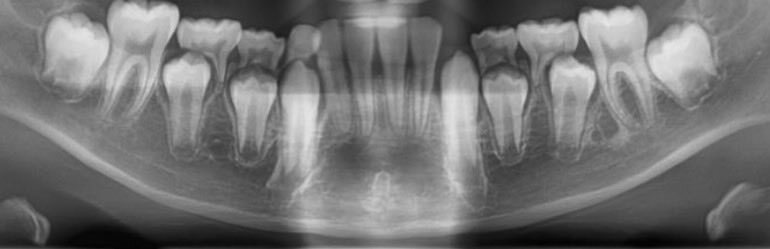

小児矯正パノラマチェック③ ①②より下顎Eを早期抜歯して5番萌出誘導とリーウェイスペース開放による7番萌出誘導を検討する その場合、4番にアダムスを設定する必要性が高くなるためD早期抜歯をまず進めてから上記進める このように先を読みながら小児矯正進めると良いと思います #TOD式小児矯正 pic.x.com/5W3jqA49NV

TODでは、小児矯正診断のタイミングを上顎1番が萌出開始された時期にしています 永久歯前歯の被蓋関係の確認が取れた上で、歯列や咬合改善をピックアップするためです これにより、出来るだけ小児矯正内に治療完結を目指しています #小児矯正始めるタイミング #TOD式小児矯正 #小児矯正で完結

TODサポートプランご利用の先生方へ いつもありがとうございます 小児矯正サポートにおいて、1点だけ注意事項があります 添付するパノラマデータは、依頼時2週間前までの撮影データがオススメです! 乳歯の歯根状況に影響されやすいからです #TOD式小児矯正 #矯正サポートプラン #株式会社TOD